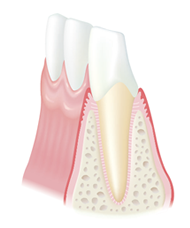

健康な状態

歯と歯ぐきの間にプラークがたまって歯ぐきが腫れ、出血しやすくなっています。歯を支える骨にはまだあまり影響がありません。